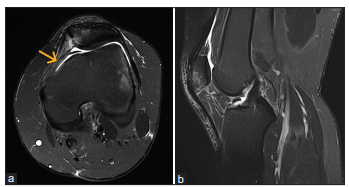

Bệnh nhân nữ, 20 tuổi, không có bệnh lý nền, bị chấn thương trong lúc nhảy – tiếp đất khi đang khiêu vũ, gây đau và biến dạng khớp gối trái, kèm theo mất chức năng vận động. Cô đến khám bác sĩ địa phương và được chẩn đoán bán trật bánh chè trái. Bệnh nhân được nắn chỉnh kín và mang nẹp bảo vệ gối [Hình 7]. Tuy nhiên, sau đó vẫn xuất hiện tình trạng trật bánh chè trái tái diễn từng lúc và đau gối kéo dài khi vận động. Bệnh nhân được chỉ định chụp cộng hưởng từ (MRI), cho thấy rách một phần dây chằng MPFL gối trái kèm theo dị vật rời trong khuyết gian lồi cầu [Hình 8]. Không phát hiện tổn thương dây chằng chéo hay sụn chêm đi kèm. Sau khi trao đổi, bệnh nhân đồng ý thực hiện phương pháp phẫu thuật xâm lấn tối thiểu như đã mô tả ở trên để điều trị tổn thương MPFL. Ca mổ diễn ra thuận lợi, và bệnh nhân được xuất viện sau 2 ngày mà không gặp biến chứng nào.

Trường hợp còn lại là một bệnh nhân nữ 13 tuổi cũng bị đau gối trái sau động tác nhảy – tiếp đất trong lúc khiêu vũ. Cô bé bị chấn thương gối trái lần đầu tiên cách đây 1 năm và đã được điều trị bảo tồn bằng thuốc kháng viêm. Sau đó, bệnh nhân hồi phục và quay lại tập luyện khiêu vũ. Tuy nhiên, bệnh nhân lại bị chấn thương gối trái lần nữa trong một lần nhảy – tiếp đất. Lần này, bệnh nhân có biểu hiện đau liên tục ở gối trái kèm theo hạn chế tầm vận động. Khi khám tại phòng khám ngoại trú (OPD), hình chụp X-quang cho thấy tình trạng bán trật bánh chè trái. MRI cho thấy rách một phần dây chằng MPFL kèm theo bong điểm bám khỏi bánh chè [Hình 10]. Phẫu thuật được sắp xếp sau khi có sự đồng thuận từ gia đình bệnh nhân. Chúng tôi đã tiến hành nội soi khớp và thực hiện thủ thuật như đã mô tả trước đó một cách thuận lợi. Bệnh nhân được xuất viện không có biến chứng và tiếp tục theo dõi tại phòng khám với phác đồ hậu phẫu giống như ca trước. Bệnh nhân hồi phục tốt, trục gối được chỉnh thẳng và có thể quay lại tập luyện mà không gặp khó chịu nào.